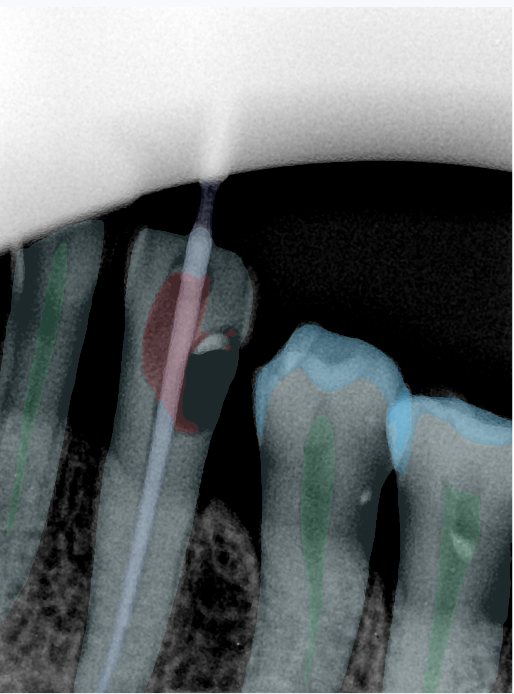

CR/DR 牙齿分割阶段记录

当前进展

- 完成了 CR/DR 牙齿相关分割训练

- 当前结果已经达到阶段预期,但仍有细节问题需要继续处理

相关测试

遇到的问题

- 训练过程中出现过 mask 下移问题

- 部分结果会出现 box 填充异常

- mask 边缘仍然有比较明显的锯齿感

参考

第二版算法问题测试